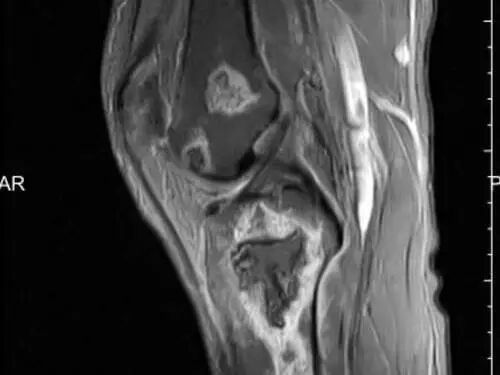

肌骨超声:无创无痛、精准度高,能清晰显示关节内结晶、滑膜增生、骨侵蚀等情况,多关节同步检查,为溶解治疗提供依据;